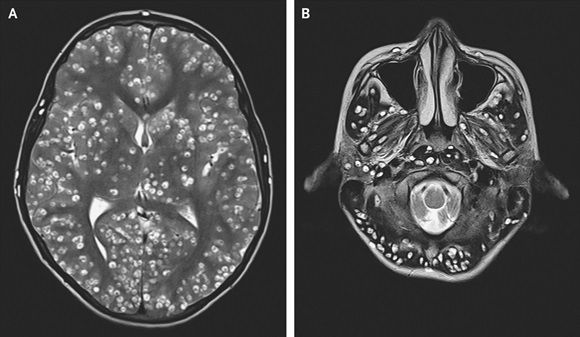

이후 병원에 실려온 소년은 생각보다 심각한 검사 결과를 마주해야 했습니다. 뇌가 수십 개의 낭종 병변으로 뒤덮여 있었던 겁니다.

이는 '신경낭미충증' 때문으로, 제대로 익히지 않은 돼지고기에 있던 기생 애벌레가 소년의 뇌로 침투해 손상시킨 것이라고 의료진은 설명했습니다.

이 사례는 최근 발간된 '뉴잉글랜드 의학저널'에 소개되며 눈길을 끌고 있습니다.